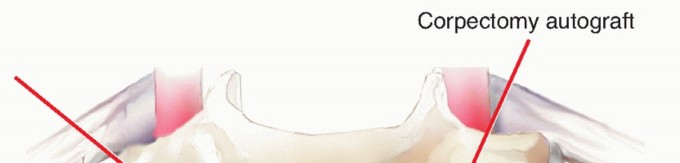

4. ## Grafting Options Autograft, allograft, or cages can be used. Autograft options include structural iliac crest or autologous fibula. Both are excellent graft materials but can be associated with significant donor site morbidity. Because of its shape, iliac crest is generally suitable for one- or sometimes two-segment corpectomy reconstruction. Fibula is favored for two- segment or more corpectomy reconstruction.8 Because of donor site morbidity issues, allograft fibula or cages filled with local autograft remain popular choices for corpectomy reconstruction. Local corpectomy bone can be used to provide the biologic stimulus for healing, allowing the allograft to serve both structural and osteoconductive roles. Local bone is packed in and around the allograft (TECH FIG 4).

### TECH FIG 4 • Local morselized autograft is packed around the strut graft and into the cleared-out uncinate regions. An additional benefit of wide discectomy is the ability to fuse the uncinate regions.